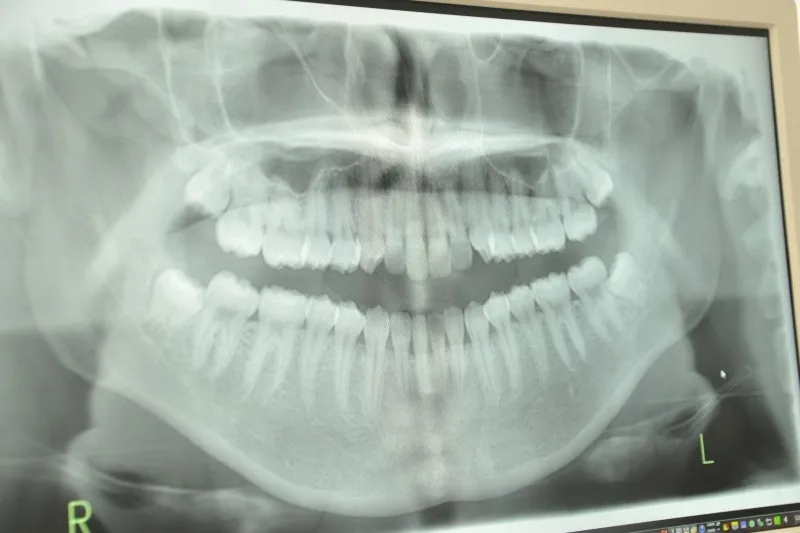

歯科医院では、歯周ポケットの深さ測定やレントゲン検査を通して、歯周病の進行度を正確に把握できます。その上で、患者様一人ひとりの症状や生活習慣に合わせた治療計画を立てるため、無理なく続けられる予防と治療が両立します。大和郡山市の歯科医院選びでは、歯周病治療の実績や患者様とのコミュニケーションを重視しているかどうかもポイントです。

具体的な歯周病治療の流れとしては、まず歯科医院での精密検査による歯周ポケットの深さ測定やレントゲン撮影が行われ、進行度に応じたクリーニングやスケーリング・ルートプレーニングなどの基本治療が実施されます。必要に応じて、歯周外科処置や再生療法も選択肢となります。これらの治療後も、日常の歯磨きや定期的なプロフェッショナルケアが不可欠です。